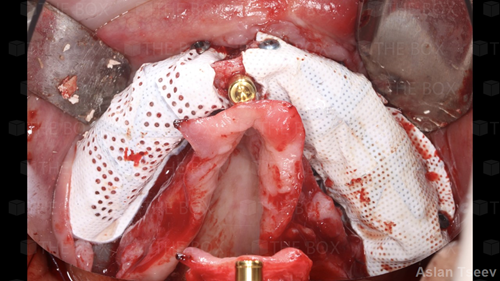

A new case was made public by Viktoria Plyeshakova check it out here.